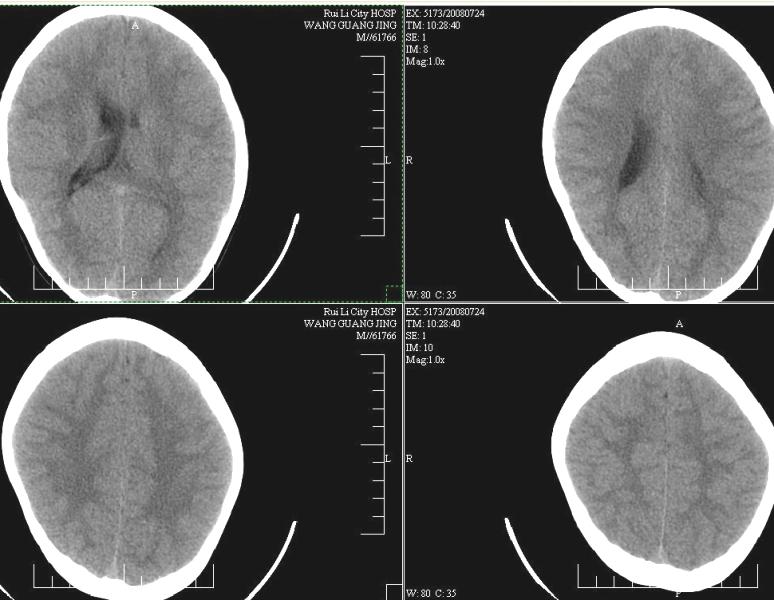

标题: PED0930:M,9岁,常感头疼有时有恶心。

透明隔移位伴右侧侧脑室扩张

透明隔居中,左侧脑室受压,建议增强或mri检查

右侧侧脑室扩张,透明隔稍左移,建议mri检查。

左侧侧脑室发育异常.(灰白质无移位.)

考虑先天性透明隔移位伴右侧侧脑室扩大。

左侧脑室较对侧小,考虑发育异常!!

右侧侧脑室扩大,考虑发育异常,建议mri检查。